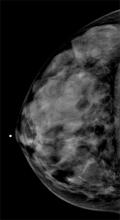

AI is also helping simplify complex tasks and help reduce the reading time on involved exams. One example of this is in 3-D breast tomosythesis with hundreds of images, which is rapidly replacing 2-D mammography, which only produces 4 images. Another example is automated image reconstruction algorithms to significantly reduce manual work. AI also is now being integrated directly into several vendors' imaging systems to speed workflow and improve image quality.